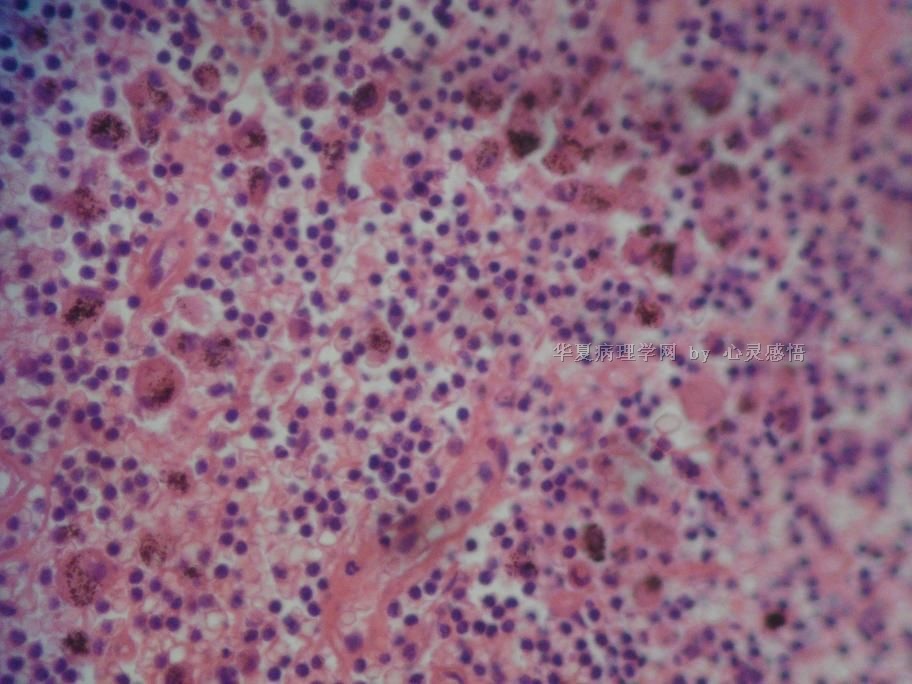

• 食道癌,淋巴结有没有转移,谢谢。图1

图1

1-6图是鳞癌。7-22图片无癌。

淋巴结没有转移

本帖最后由 于 2010-11-17 20:19:00 编辑  图14,19有转移

没有转移。

没有转移,食道旁的淋巴结和肺旁的淋巴结相似,含有吞噬细胞。